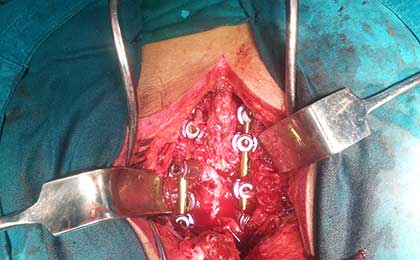

INTRA OP SPINE FIXATION

DORSAL SPINE FIXATION INTRA OP

traumatic spine fix intraop